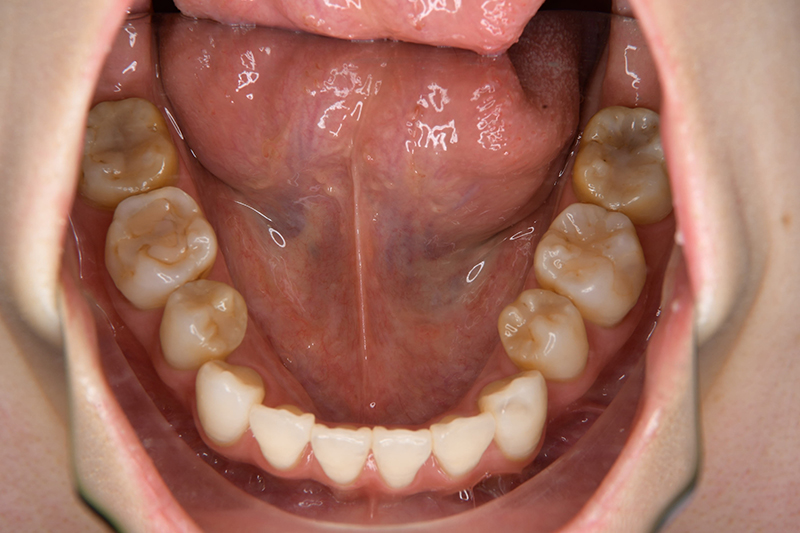

FP・IOP

口腔内所見 over jet 4.0mm、over bite 2.0mm、臼歯関係Ⅰ級、犬歯関係Ⅱ級で上顎前歯は唇側傾斜を呈しており、上下顎前突の様相を呈していた。